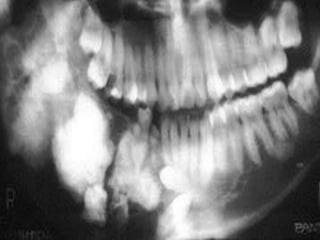

Odontogenic Keratocyst

Odontogenic Keratocyst 11% of jaw cysts

 Radiographically

 Well-marginated, radiolucency

 Pericoronal, inter-radicular, or pericoronal

 Multilocular